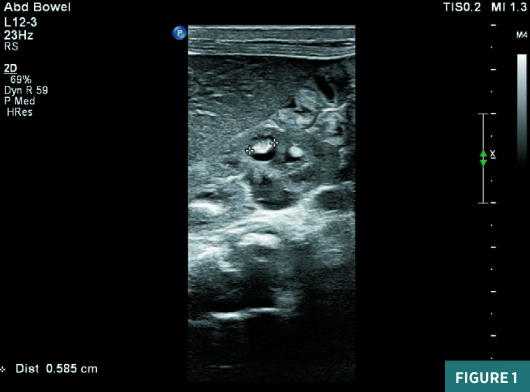

On renal ultrasound, the right kidney measured 4.5 cm X 2.5 cm and the  left kidney measured 4.3 cm X 2.6 cm. Diffusely increased echogenicity  involving the base of the renal pyramids was noted bilaterally with these  echogenic foci measuring approximately 4 to 5 mm and were suggestive of  medullary nephrocalcinosis. Renal cortical caliber was normal bilaterally.  There was bilateral dilatation of pelvicalyceal system with anteroposterior  diameter of the renal pelvis measuring 11 mm on the right and 9 mm on the left  (Figures 1 to 4). There was moderate left hydroureter and no evidence of  hydroureter on the right side. The renal pelvic dilatation was consistent with  bilateral ureteropelvic junction obstruction, which needed interval follow-up  prior to intervention. No urinary bladder abnormality was noted.

Nephrocalcinosis secondary to primary hyperoxaluria/oxalosis, renal tubular acidosis, or urinary tract infections is rare in newborns, although these conditions may present a few months after birth.4 On ultrasonography, in patients with nephrocalcinosis, the renal pyramids are echogenic and may or may not have associated shadowing, which depends on the size of the calcifications. The size, echogenicity, and pattern of the medullary echogenic foci point toward medullary nephrocalcinosis. In individual cases, it can be difficult to distinguish between medullary nephrocalcinosis and renal calyx calculi.